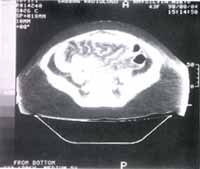

Figura 7. Tac abdominal. S.N. paciente de 32 años, con un lupus que se inició a los 18 años. Presentó una vasculitis del intestino delgado.

Se observan dilataciones de las asas intestinales e irregularidad de la mucosa.